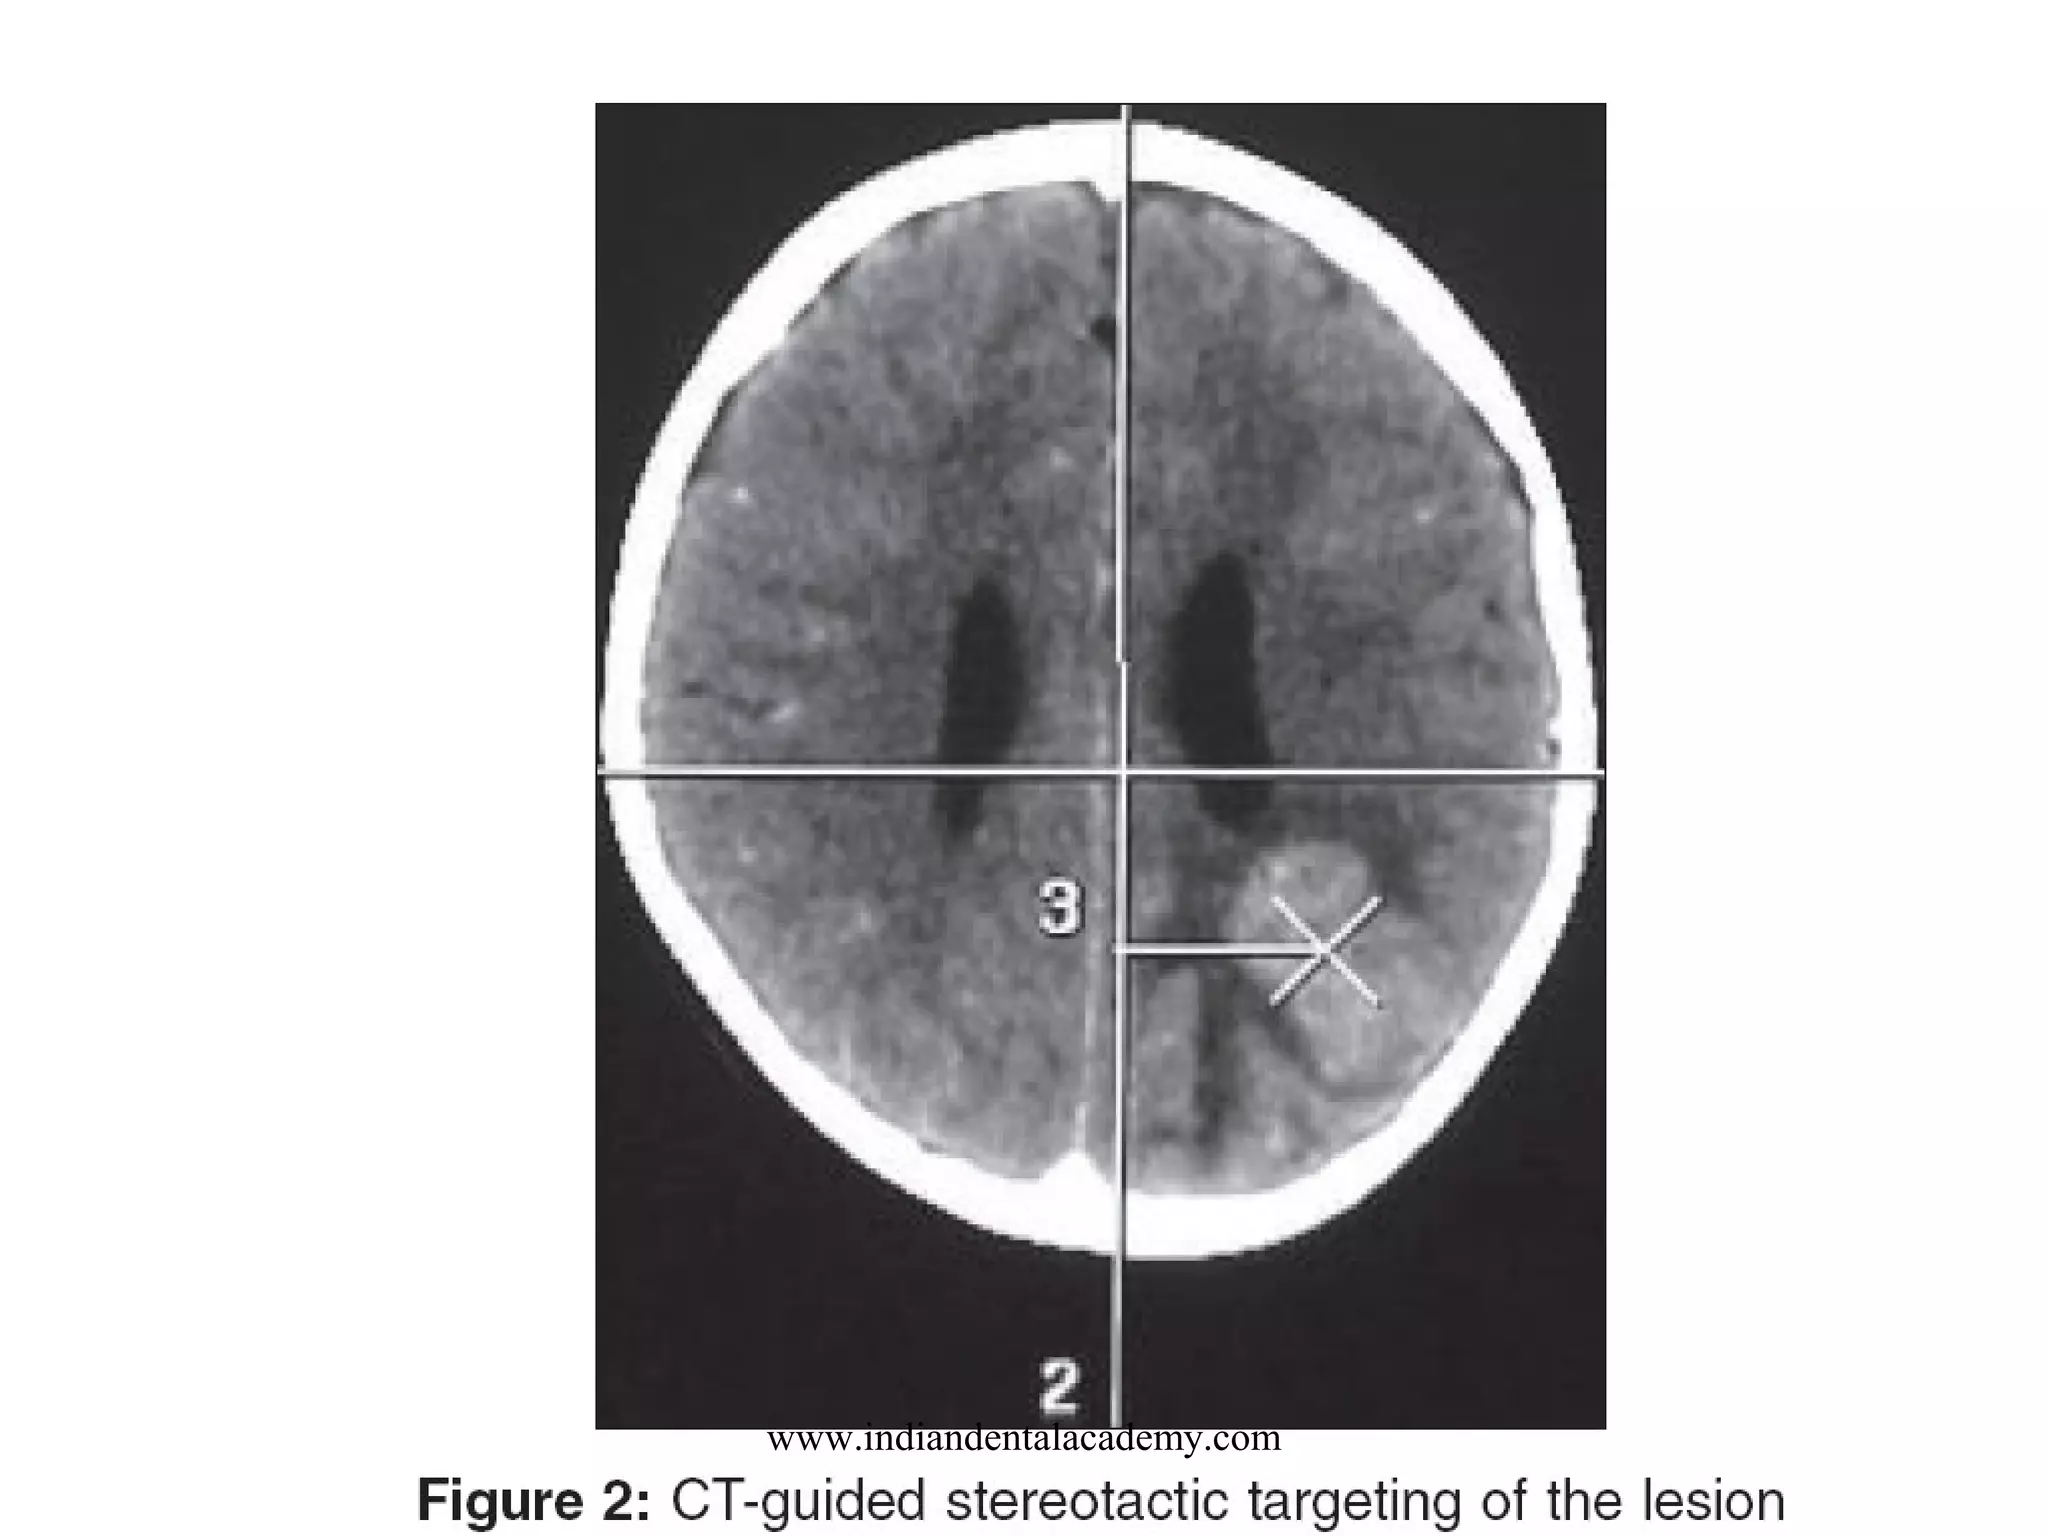

STEREOTACTIC

www.indiandentalacademy.com

Stereotactic system use

•

Biopsy of intracranial lesions

Aspiration of cysts

Laser microsurgery

Aspiration of brain abcess